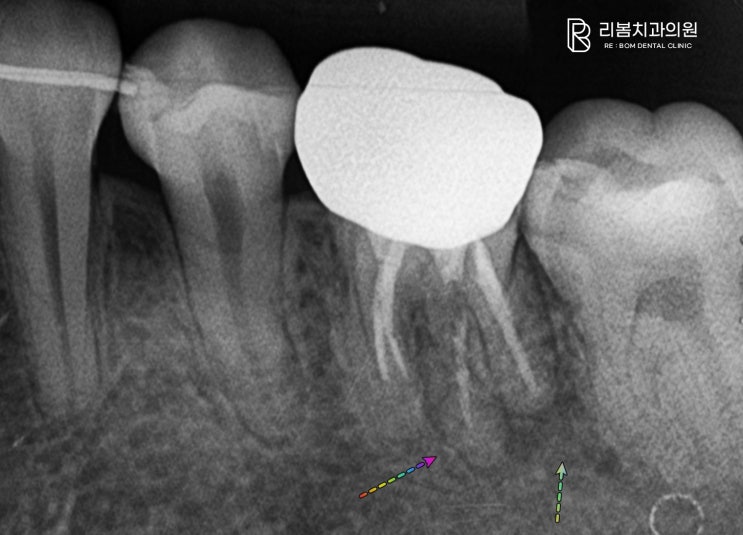

발치 될 뻔한 어금니, 재신경치료로 살리기 인천 송도 치과

안녕하세요, 인천 송도 치과 의사 박현호입니다. 치아와 치주조직 그리고 잇몸은 서로 밸런스를 맞추며 구...